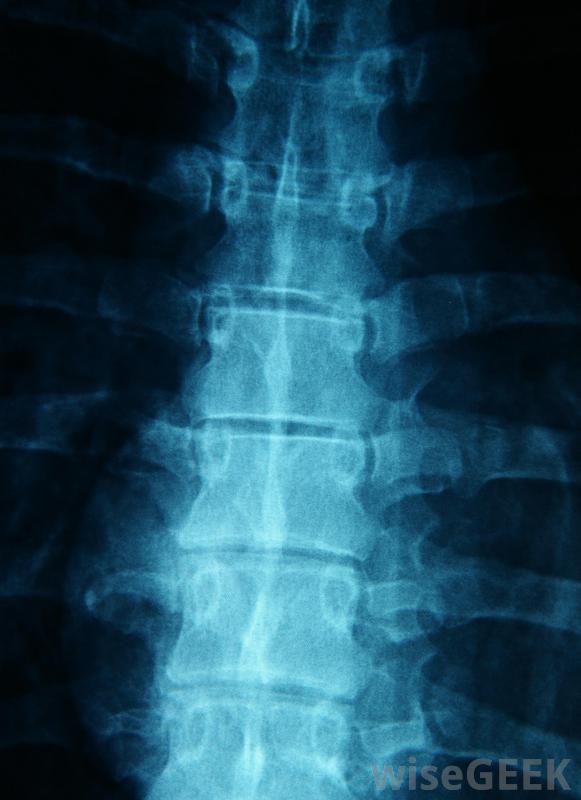

医生可以用X光片检查脊柱是否有异常。摇摇晃晃最明显的影响是它对姿势。脊柱前凸的人会弓形向前,骨盆向前倾斜,臀部显得更加突出。如果弯曲过度,会影响患者的活动能力。疼痛也是一种常见症状,因为异常的弯曲会对周围的韧带和肌肉造成压力

患有病态肥胖的人有时会出现摇摆不定。在诊断前凸时,医生通常会从病史开始,包括问题发生的时间、进展的程度,以及可能的影响因素。他或她通常还会进行身体检查,以确定患者的活动范围,并确定曲线是否灵活,当患者向前弯曲时,曲线在哪里反转,在哪里弯曲,在哪里不弯曲。任何神经系统症状,如疼痛、麻木,或者会对刺痛感进行复查。医生可能会感觉到脊椎,或者在某些情况下使用X光片和其他测试来查看曲线的范围并寻找异常。